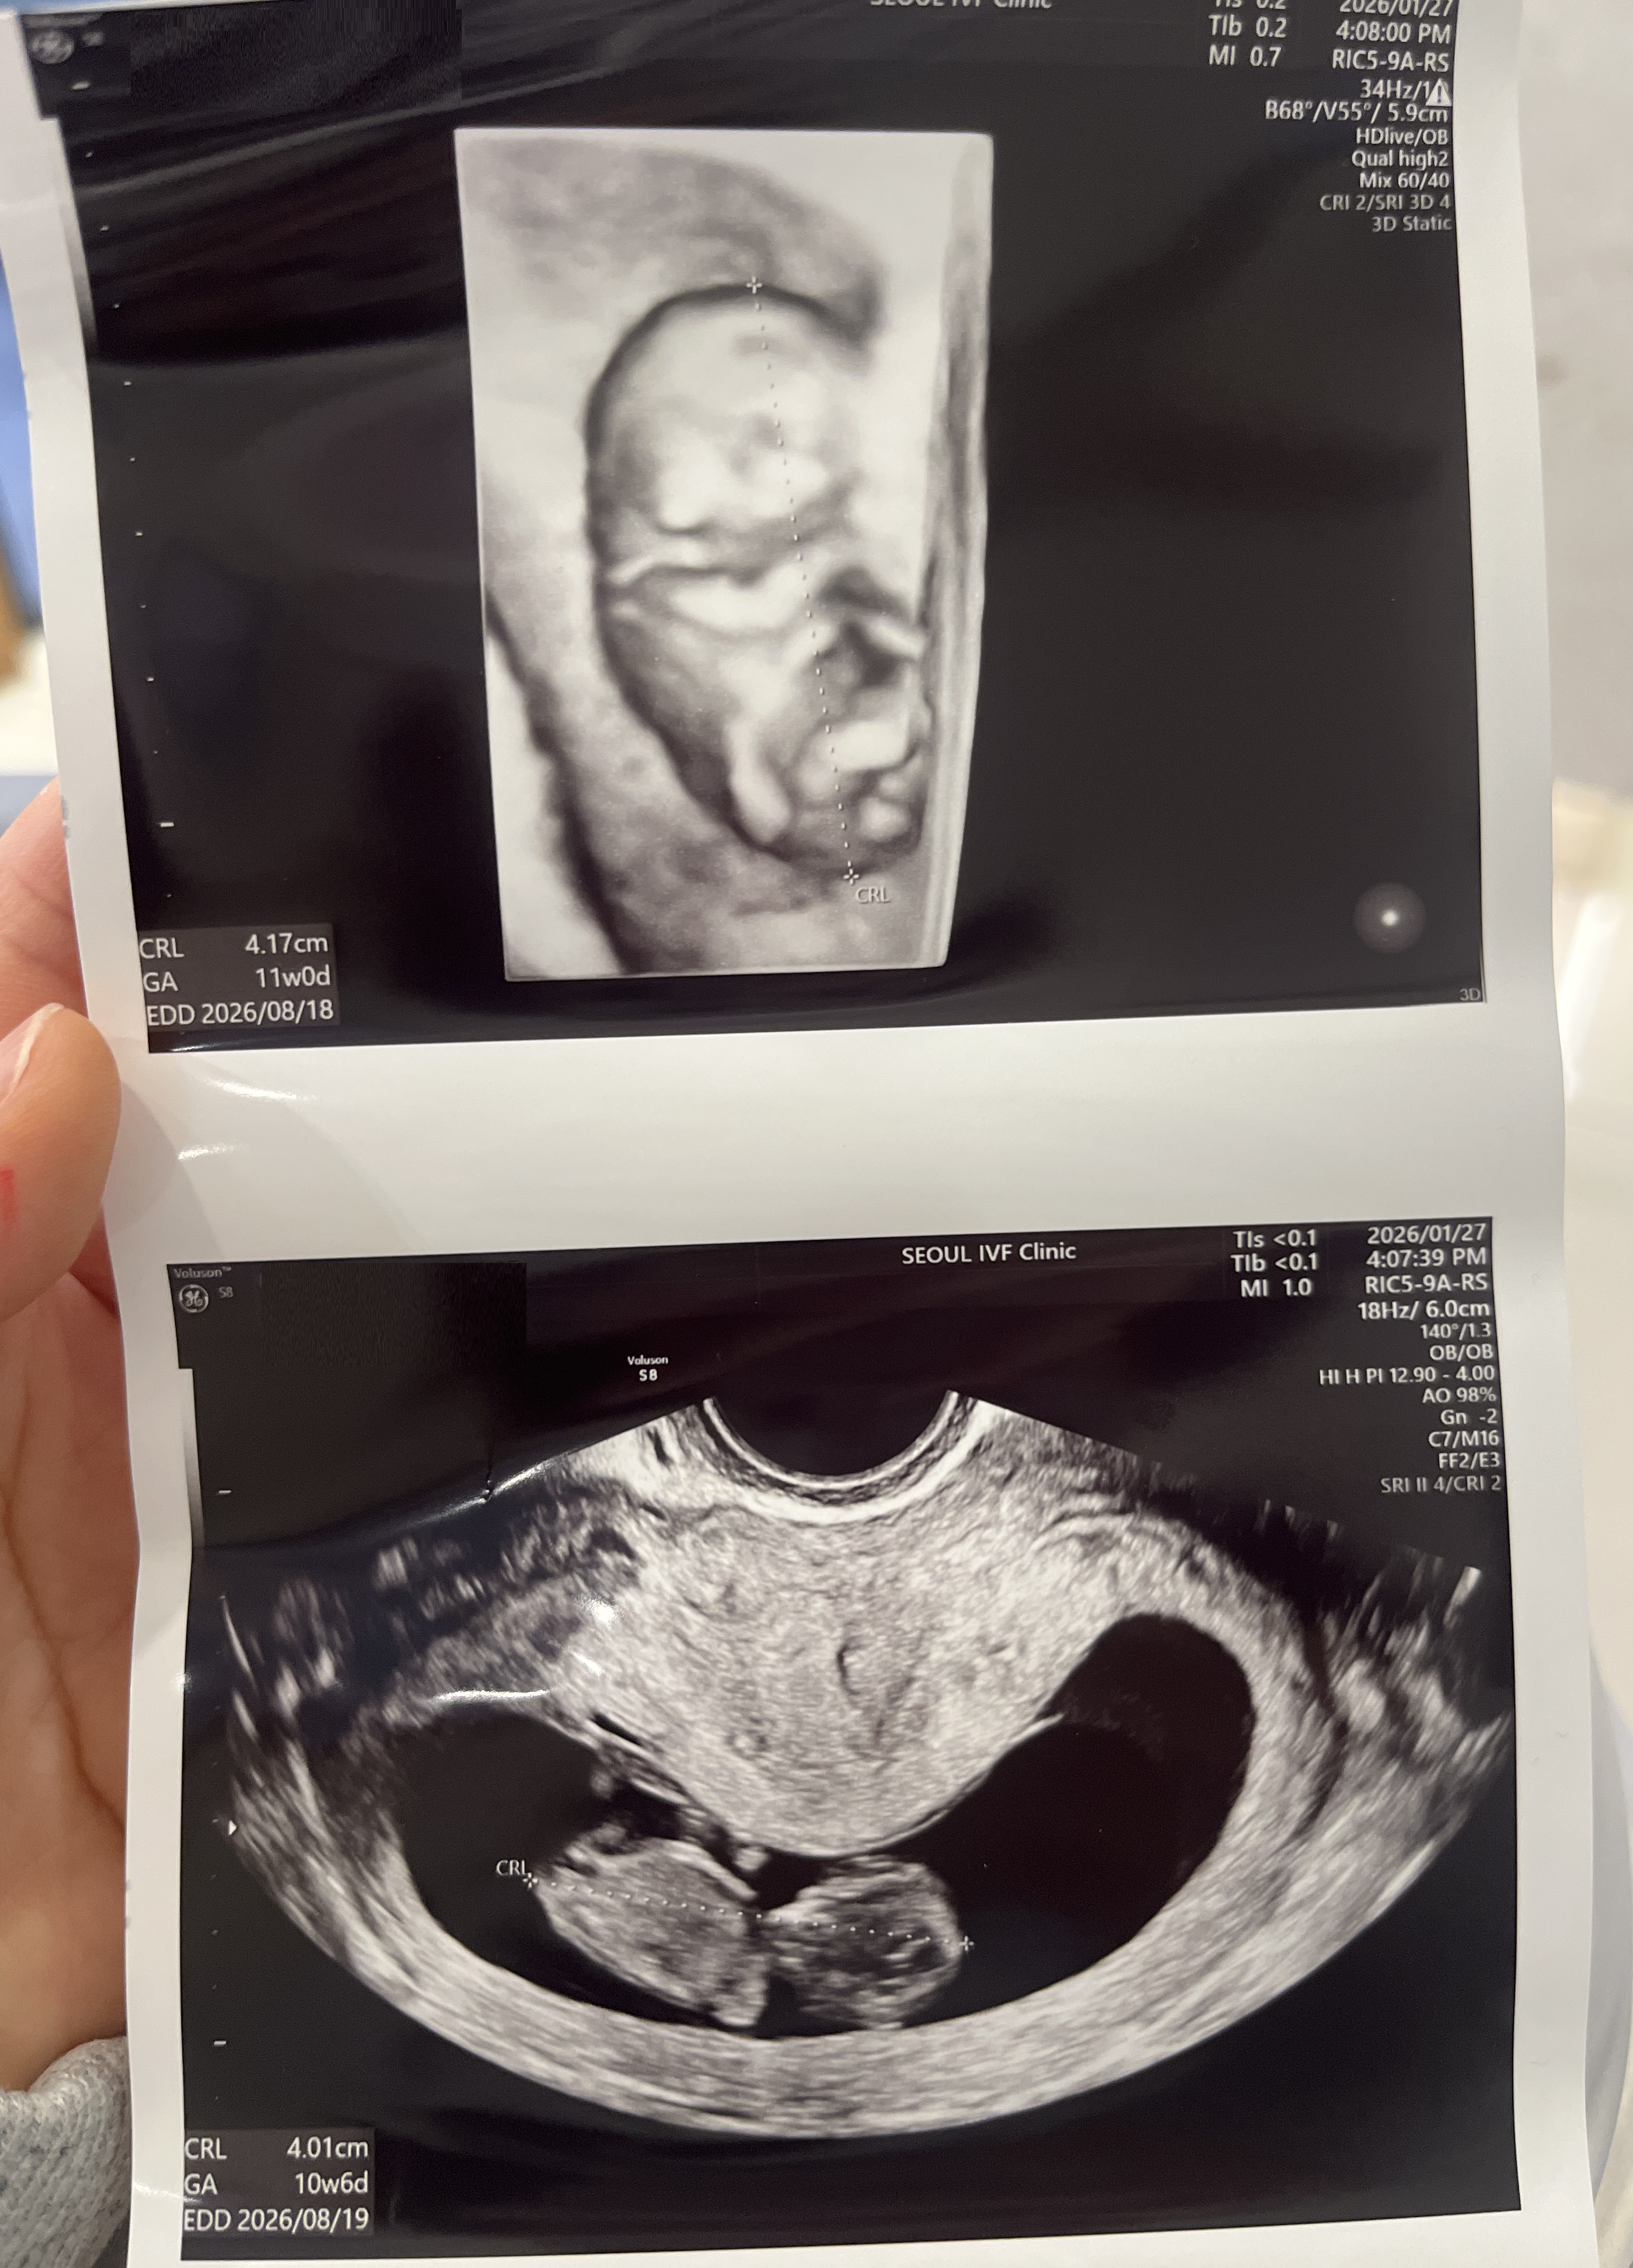

| 가슴 떨리는 임신 이야기를 공유해 주세요. | 자연임신을 시도한 후 시험관 1차 시술로 임신에 성공하게 되었습니다. 첫 심장소리를 들었던 날이 가장 기쁘고 벅찼던 순간으로 기억에 남습니다. |

| 치료 도중 느꼈던 가장 기뻤던 순간과 절망적인 것들은 무엇인가요? 잊지 못할 경험이 있나요? | 가장 기뻤던 순간은 아기의 심장소리를 처음 들었을 때였고, 가장 슬펐던 순간은 인공수정 2차가 실패했을 때였습니다. |